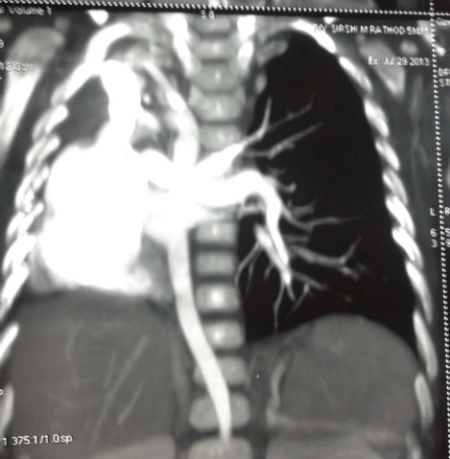

A 3-day old female neonate born at full term through normal vaginal delivery presented with had absent anal opening; she was passing stool from vestibule. The antenatal period was uneventful, but there was no record of ANC or antenatal ultrasonography. Local examination revealed presence of persistent cloaca. There was no palpable abdominal lump. Her respiratory rate was normal and she was maintaining adequate saturation on air. On auscultation, breath sounds were absent on right side. The chest x-ray reveled opacification of the right hemi thorax with mediastinal shift. In view of her stable cardio- respiratory status, we decided to first do a transverse colostomy for fecal diversion before further investigation for her lung condition. The perioperative course was uneventful. Postoperatively the baby was investigated for right hemithorax opacification. She underwent 2D- Echocardiogram which showed absent right pulmonary artery, tiny PDA, small ASD. Patient was discharged on 5th postoperative day on oral feeds with healthy functioning stoma. She was put on distal loop washouts and observation. Her cardio-respiratory status continued to be stable. On follow-up at 6 months age, CT angiography chest was done which was suggestive of agenesis of right pulmonary artery and pulmonary vein, right pulmonary agenesis and aberrant right subclavian artery (Fig. 1). We did a diagnostic bronchoscopy that revealed complete absence of right main bronchus and trachea continued as a single left bronchus with normal distal branching confirming the diagnosis of right lung agenesis. Since patient is asymptomatic, no intervention has been done for her lung condition. She is now waiting for definitive surgery for cloaca.

Figure 1: CT angiogram |